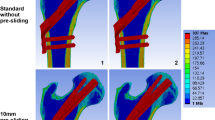

Figure 3 illustrates the interfragmentary stress distribution. Among the fracture surfaces, stress was mainly concentrated around the screws and in the medial femoral neck. The interfragmentary stress was 19.02 Mpa, 18.25 Mpa, 21.12 Mpa, 20.71 Mpa, and25.80 Mpa in superior, central, inferior, anterior, and posterior models respectively. As the distance between the internal fixation and the medial cortex increased, so did the area of force on the bone.

The distribution of equivalent stress and shear force was displayed in Fig. 4. Shear stress primarily occurred at the contact between the fracture surface and the internal fixation. The equivalent stress was 70.9 Mpa, 74.09 Mpa, 89.27 Mpa, 75.65 Mpa, and 109.7 Mpa in superior, central, inferior, anterior, and posterior models respectively. The shear stress of internal fixation was 13.06 Mpa, 17.53 Mpa, 21.12 Mpa, 18.54 Mpa, and 22.11 Mpa in superior, central, inferior, anterior, and posterior model respectively. Total displacements were 1.399 mm, 1.276 mm, 1.345 mm, 1.306 mm and 1.336 mm for superior, central, inferior, anterior, and posterior models respectively.

The trend of equivalent stress, shear stress, and total deformation is described in Fig. 5. According to the results, the central model exhibited the smallest stress and displacement, with the exception of the superior model. A comparison of the superior model with the central model revealed that equivalent stress and shear force in the upper model were low, but the displacement and interfragmentary stress were high. This indicated that more stress was transferred to the bone near the fracture, resulting in increased displacement of the model. In general, the total displacement is positively related to the overall stability of the model. In all models, the largest stress area appeared in the superior model.

Equivalent stress, shear stress, and total deformation were recorded in our study. Equivalent stress cloud diagrams can help us understand the force distribution very well. It uses stress contours to represent the stress distribution within the model, which clearly depicts how a result varies throughout the model, allowing the analyst to quickly identify the most dangerous areas of the model. In the model, the role of internal fixation is to take up and distribute the stress. In other words, the lower the stress value of the screw, the lighter the color of the stressed area, the higher the stability, because excessive stress increases the fatigue of the material. In our research, equivalent stress primarily occurred at the contact between the fracture surface and the internal fixation, which was consistent with the force situation (Fig. 4). However, we found that there was no stress concentration region in the superior model, indicating that the internal fixation did not play a role in dispersing the stress. Combined with the stresses on the fracture surface, our hypothesis was further confirmed. The internal fixation stress of the superior model was 4.3% smaller than that of the central model. While, the interfragmentary stress of the superior model was 4.2% larger than that of the central model. We also observed that the superior model had the largest range of forces on the fracture surface. Generally, the larger the area under stress, the more bone deformation occurs and the less stable it is. Also, our data showed the displacement of the superior model increased by 9% compared to the central model. Clearly, the superior model's internal fixation system was ineffective.

Femoral head pressure load can be separated into compressive and shear stresses based on the central axis of the neck and fracture surface. Axial compressive stress can promote fracture healing. The presence of shear stress increases the relative slip between fracture surfaces, which can lead to the failure of the fixation model. Nonetheless, previous finite element analyses did not include shear stress results. In our study, the area of concentration of shear stress varied with the location of the internal fixation. This eccentric placement may lead to uneven forces, thus weakening the compression effect on the fracture surface. The superior placement kept the screw away from the pressure trabeculae and did not effectively support and share the pressure from the femoral head. Generally, the shear stress area reflects the eccentricity of the screw. In the anterior position, the shear resistance area was the largest, indicating the greatest eccentricity at the moment (Fig. 4). According to our hypothesis, this was due to the anteversion of the femoral neck. As the bolt was placed anteriorly, the plate was located on the posterior side of the proximal femur, resulting in a large angle between the bolt and the axis of the femoral neck. Results indicated that the superior model had the lowest shear stress, but its shear resistance area was larger than that of the central and inferior model. Combined with the shear resistance area and shear stress, the central location was more preferable.We combined all the results into a dotted line graph so that we could find patterns (Fig. 5). Based on the previous analysis, we considered the superior model to be the most unstable. And the central model exhibited better biomechanical performance in terms of equivalent stress, shear stress, and total deformation. This result was in accordance with the previous findings in the coronal plane.